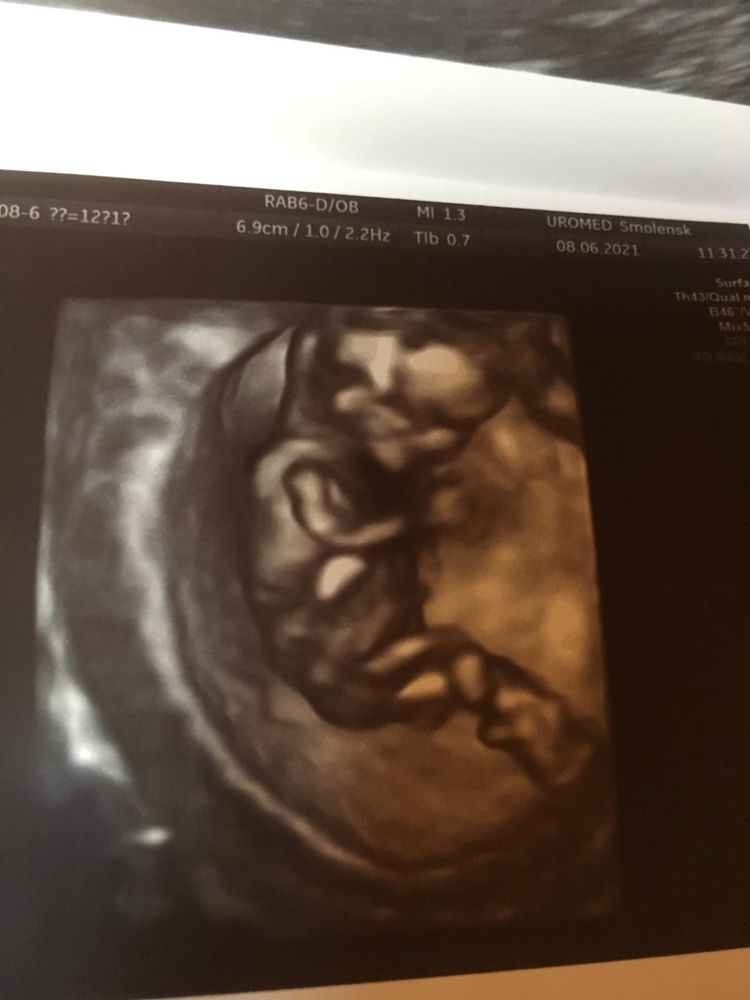

Сегодня были на первом УЗИ. Всё у нас замечательно! И нос, и шея, и кровоток. По месячным 12+1, по узи 13+1. Плацента по передней стенке посерёдке. Скорей всего мальчик, как мы и хотели!

Не нужно переживать, всё прекрасно! Только одно смущает врача, шейка короткая, всего 35мм. Эрозия же, во всю шейку. Не знаю, на сколько это опасно?